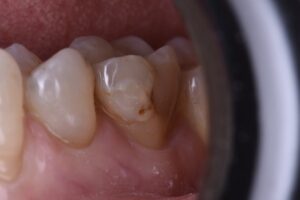

March 25, 2021 Not quite a Class V, but gnarly enough (near pulp exposure). #GC #Essentia U Previous Post Next Post